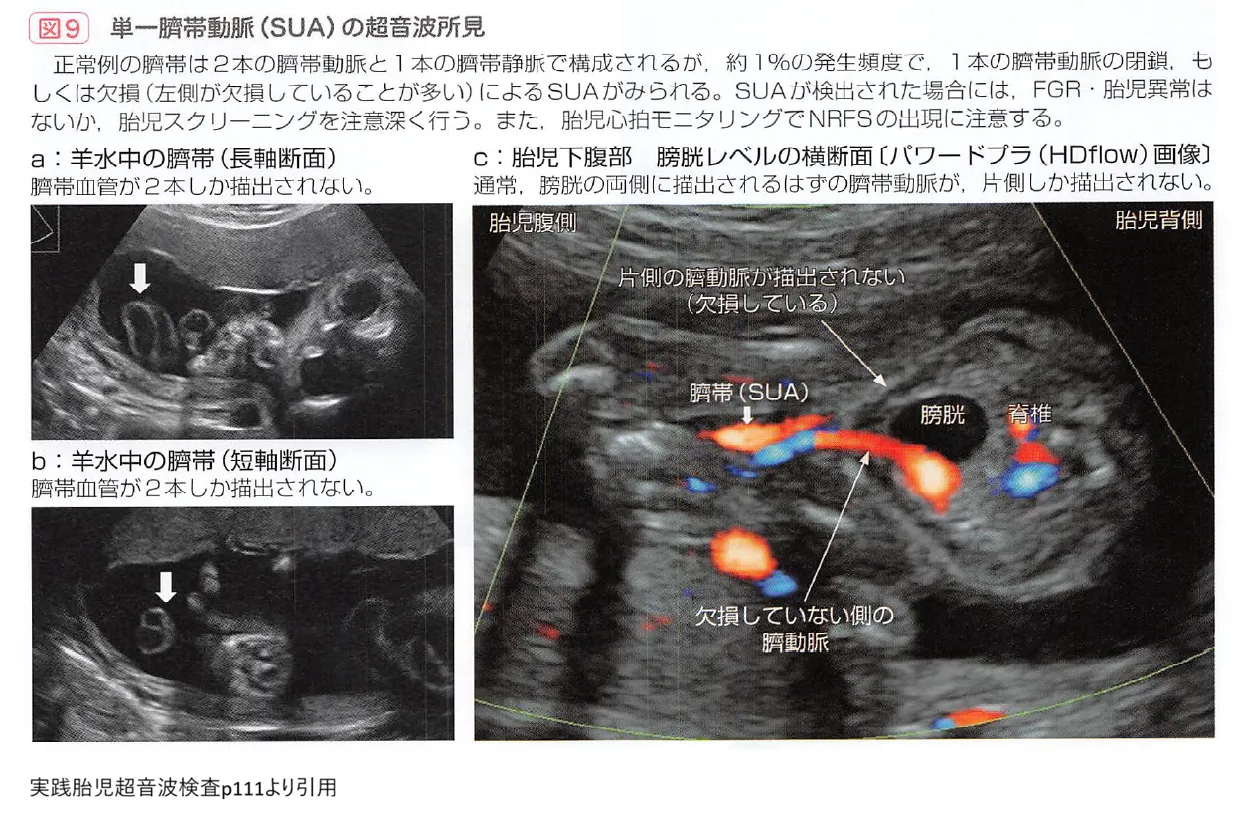

2. 単一臍帯動脈(SUA)

通常、へその緒には2本の動脈と1本の静脈がありますが、動脈が1本しかない状態を指します。ダウン症を含む染色体異常や、心臓・腎臓の奇形を合併するリスクが上昇します。